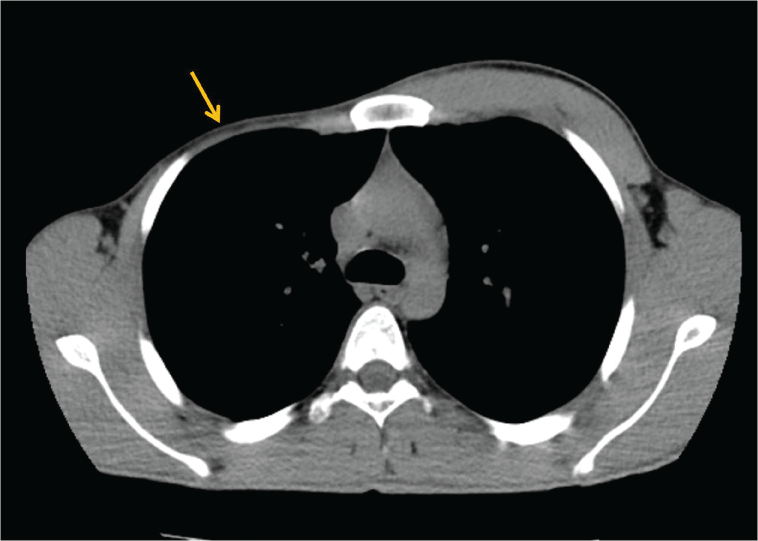

A 20-year-old male patient was admitted to our department due to asymmetrical appearance of the right chest wall. On physical examination, it was seen that right chest wall was asymmetrical and there was right nipple hypoplasia and syndactyly between third and fourth fingers in the right hand. Chest computed tomography (CT) demonstrated the absence of right pectoralis major muscle (Figure 1). No bone anomalies were found.

Figure 1: Axial chest CT image demonstrates the absence of right pectoralis major muscle (arrow).